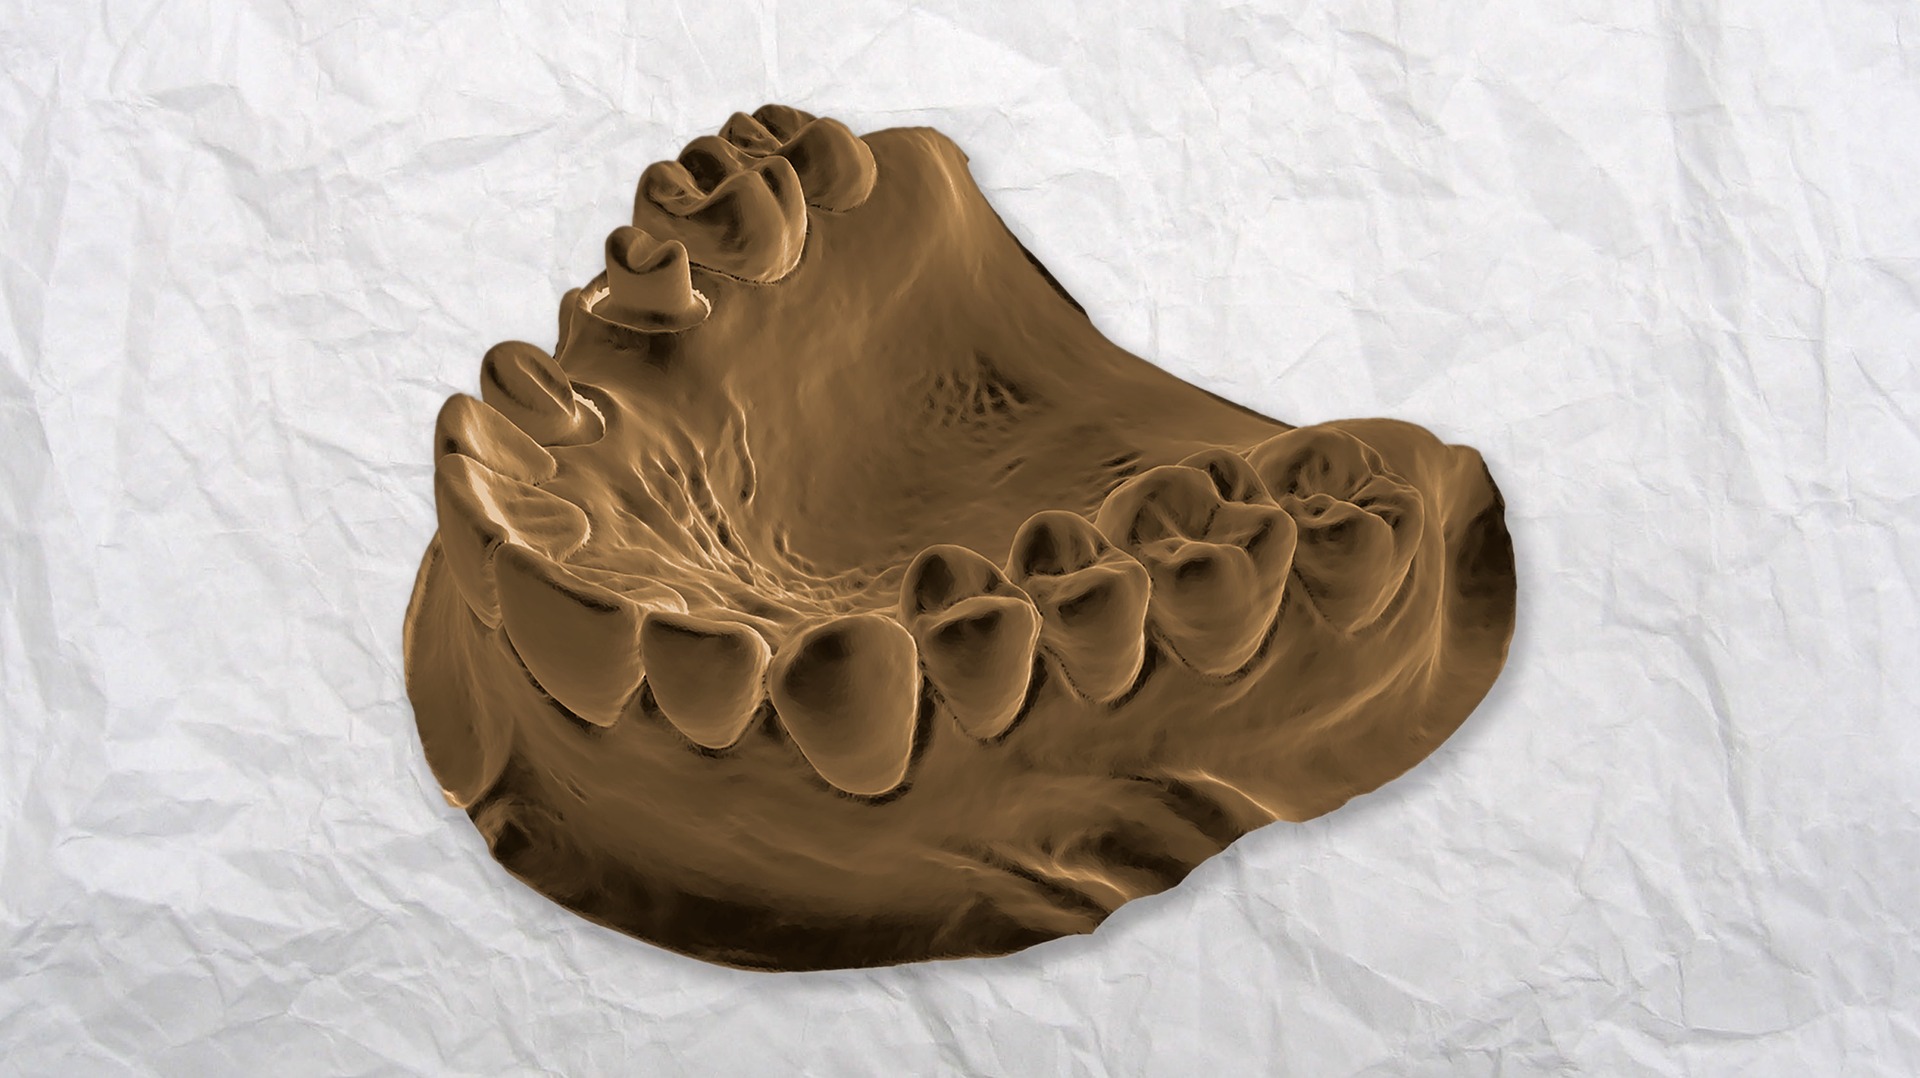

Dbanie o własne zęby jest bardzo ważne. Niestety nierzadko po czasie okazuje się, że za …

Dbanie o własne zęby jest bardzo ważne. Niestety nierzadko po czasie okazuje się, że za …

Dbanie o własne zęby jest bardzo ważne. Niestety często po czasie ujawnia się, że za …

Zdrowe zęby, ładny uśmiech to powód do dumy. Ponieważ zęby towarzyszą nam przez całe życie …

Stomatologia rozwija się bardzo szybko. Nie mamy już problemów, żeby zachować na długo piękny uśmiech. …

Zła dieta, nadwyżka cukru mogą wywoływać pruchnicę, a w konsekwencji większe braki w zębach a …

Marzeniem wielu z nas są piękne, białe zęby. Nie tylko poprawiają wizerunek ale powodują że …